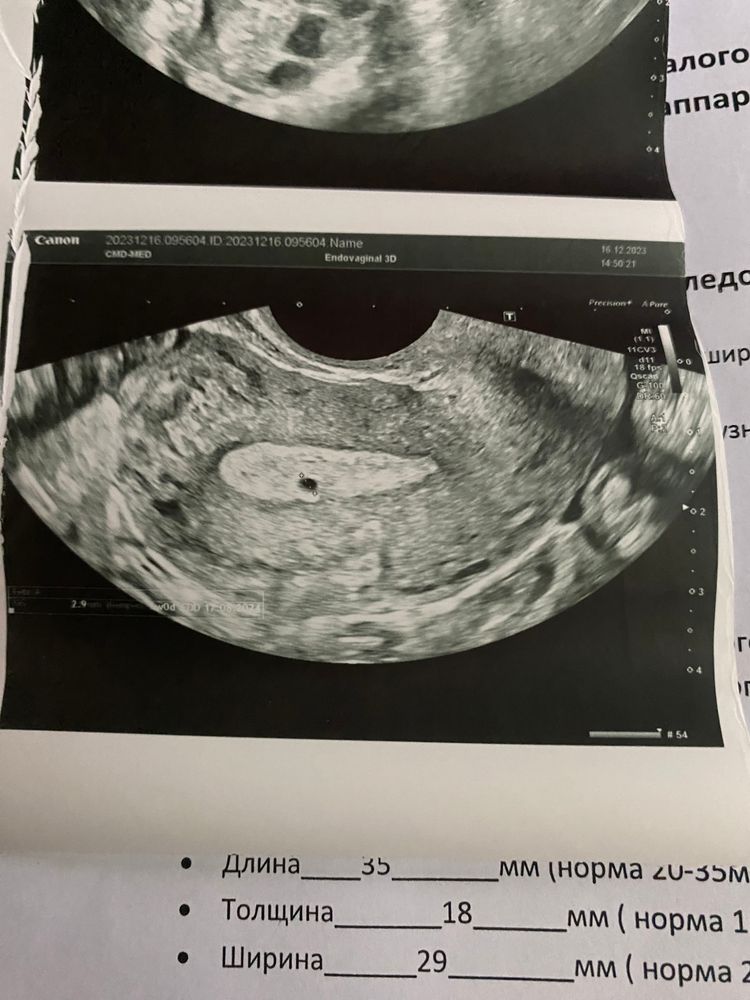

эндометриоидный ход может быть

В эндометрии? Может это полип?